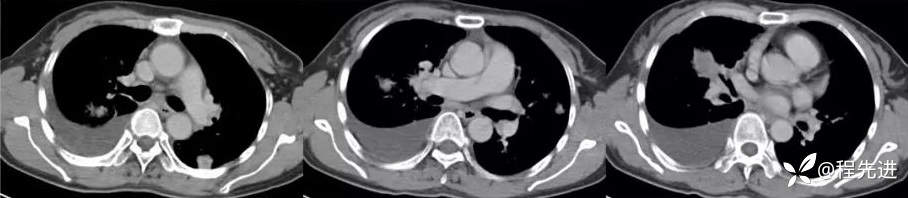

纵隔窗

增强动脉期

增强静脉期